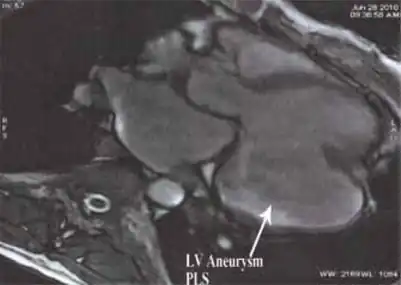

MRI showing the posterobasal left ventricular aneurysm